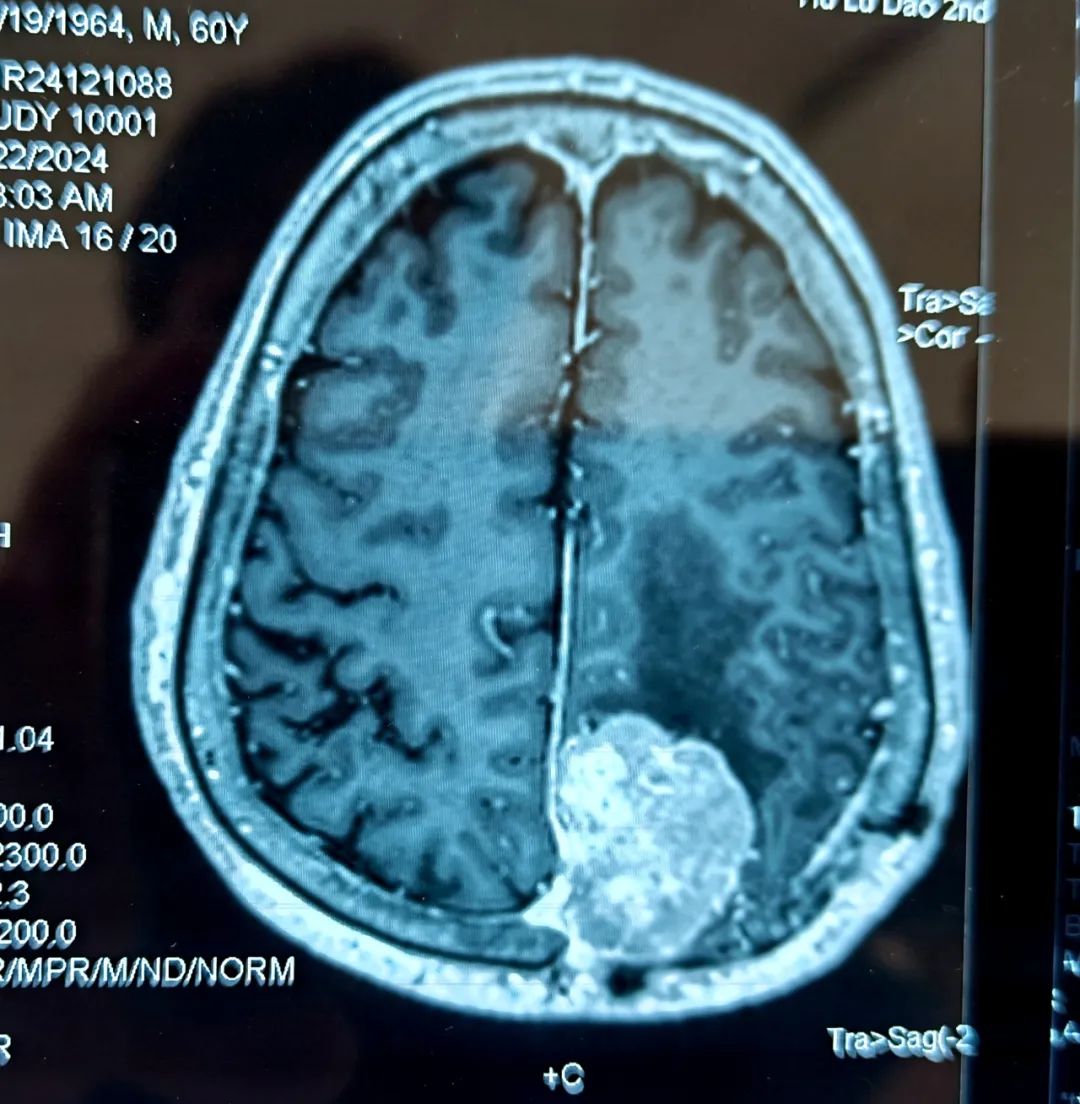

患者為60歲男性,十年前在北京某醫(yī)院行右頂部矢狀竇旁腦膜瘤切除術(shù),因腫瘤侵蝕顱骨,當(dāng)時切除腫瘤后同時給予部分顱骨切除一期顱骨修補(bǔ)術(shù),病理診斷為非典型腦膜瘤,術(shù)后未行放療,也未定期復(fù)查CT及MRI。三個半月前,患者因腦梗塞住院,檢查時卻意外發(fā)現(xiàn)腦膜瘤復(fù)發(fā),且腫瘤最大直徑已達(dá)5.2cm,屬于巨大腦膜瘤。

- 患者術(shù)前核磁 -

情況緊急,神經(jīng)內(nèi)科立即邀請神經(jīng)外科桑文淵主任會診。桑主任經(jīng)過詢問患者病史、查體、閱片后,明確復(fù)發(fā)腦膜瘤的診斷,并與患者家屬仔細(xì)溝通,表明腫瘤體積巨大且患者有頭痛癥狀,需要待腦梗塞病情穩(wěn)定后再次行手術(shù)切除腫瘤。經(jīng)過耐心的病情剖析,家屬對于手術(shù)的必要性表示理解。